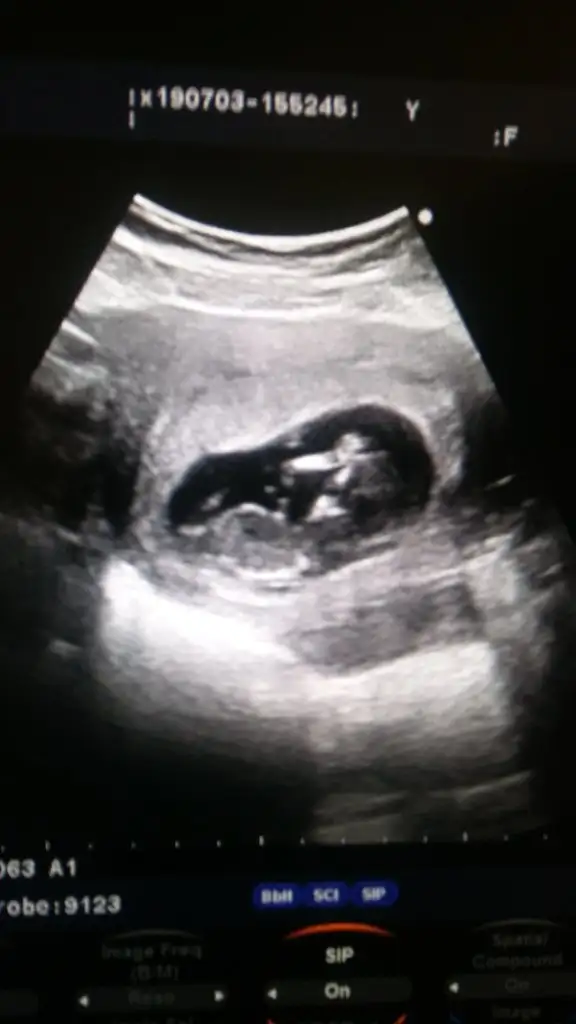

Kizlar merhabalar bizde doktordan geliyoruz oglusumuzu gördük doktorumu degistirdim yeni doktorumda erkek dedi ilk 12. Haftada ögrenmistim erkek oldugunu cok sakin uyuyordu yavrum Allahim baktikca bakasi geliyor insanin yeni ciciler bile aldik simdiden 4 gün ileriden gidiyor bizimkisi göbüşünü bile gördük😍😍😍😂😂😂

Herkese merhaba benim sat 11 nisan a göre 12+0 haftalık hamileyim yarın ikili testim var cinsiyet konusunda hiç bir tahmin vs yok hafif lekelenmem vardı doktor ona baktı ikili test içinde yarına sıra verdi buda benim minnoşum dünkü fotoğrafı çokta net değil ama olsun 😊